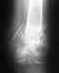

Противопоказаний по здоровью нет. Наложение гипса проходит при фиксации стопы с "выворотом" во внутреннюю сторону. После наложения гипса делается повторная рентгеноскопия на предмет "правильного" сопоставления частей костей. Рекомендовано: находиться с гипсом в течении 8 недель с промежуточными рентгеноскопией через 6 недель и наложением новой гипсовой повязки. При этом врач обозначил один момент: когда будет чувство давления под гипсом, ослабить повязку путём раздвижения частей гипсовых шин и новой перевязки. При наложении гипса отёк присутствовал в месте перелома (район голеностопного сустава) и чуть выше. Однако ежедневно отёк увеличивается как по объёму, так и площади распространения. На третий день отёк распространился до колена, т.е. загипсованная берцовая часть. Часть стопы не загипсована и на ней: тыльной части стопы и пальцах отёк с гематомами и посинением кожного покрова. Давления отёка на гипсовую повязку я не чувствовал из-за постоянных болей и жжении в этом месте, но обнаружил визуально. Сделал рекомендованную врачом перевязку. Вопрос: нормален ли такой отёк (фото 3 дня прикрепляю) либо следует внепланово обратиться на осмотр? P.S. Ногу держу слегка приподнятой, как в положении лёжа, так и сидя (по инструкции)